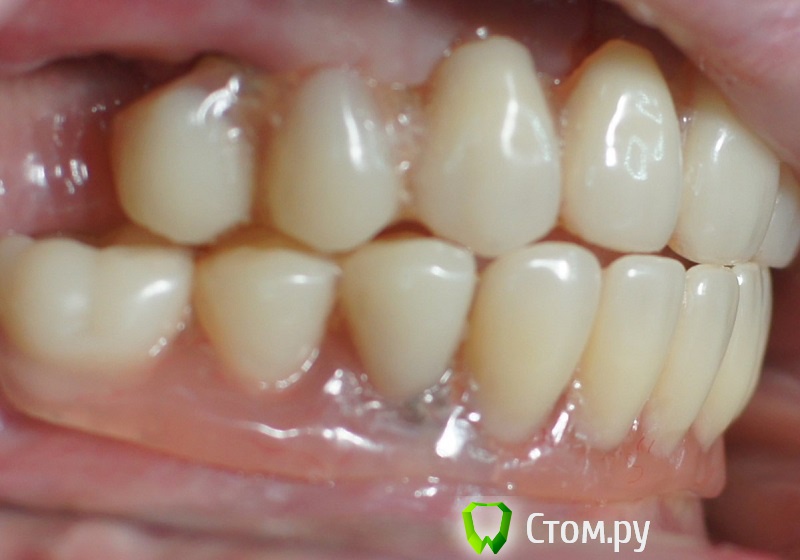

rin3225 Опубликовано 8 октября, 2014 Поделиться Опубликовано 8 октября, 2014 У пациента было желание сделать красивые зубы и улыбку!Проблема заключалась в массивной верхней челюсти , глубоком перекрытии и пациент не мог уйти без зубов! Отлив модели и выставив в центральную окклюзию было понятно, что без удаления всех зубов и поднятия прикуса с данной проблемой вопрос не решится. Обговорив все нюансы с пациентом,и получив согласие, было запланировано. заранее изготовлены акриловые протезы, предложено удаление всех зубов с одномоментной установкой имплантатов, внутриротавая сварка для первичной стабильности имплантатов и немедленная нагрузка 16 Ссылка на комментарий

rin3225 Опубликовано 8 октября, 2014 Автор Поделиться Опубликовано 8 октября, 2014 Видел… Видел…У этих людей тоже нарушение в концепции?Я не собирался повторять то о чем Вы говорите! Просто сделана первичная стабильность имплантов с немедленной нагрузкой, в дальнейшем это будет несьемная конструкция с цементной фиксацией. Балка не служит опорой для протеза и в дальнейшем будет убрана. Ссылка на комментарий

ILGAMSA Опубликовано 8 октября, 2014 Поделиться Опубликовано 8 октября, 2014 А я бы фронт внизу оставил. Работу только сделана?Тогда ждем фото и Рентгены через полгода, год. 5 Ссылка на комментарий